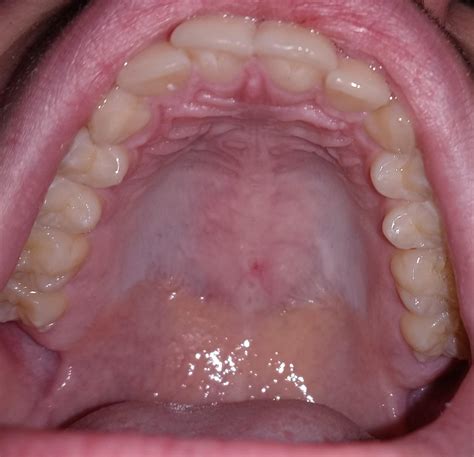

The roof of the mouth, also known as the palate, is divided into two parts: the hard palate and the soft palate. The hard palate is the bony front portion, while the soft palate is the muscular back portion. The hard palate is covered by a mucous membrane, which can sometimes develop discolorations, including a white roof of mouth.

A white roof of mouth can be caused by various factors, ranging from minor issues to more serious conditions. Some of the most common causes include:

• Oral Thrush: This is a yeast infection caused by the Candida fungus. It can lead to white patches or a white roof of mouth.

• Leukoplakia: This condition involves thick, white patches that can develop on the roof of the mouth and other areas inside the mouth. It is often painless but can be a sign of precancerous changes.

• Lichen Planus: This is an inflammatory condition that can cause white lines or patches on the roof of the mouth and other mucous membranes.

• Oral Lichen Planus: This is an inflammatory condition that can cause white lines or patches on the roof of the mouth and other mucous membranes.